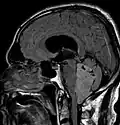

Les épendymomes supratentoriels (SE) représentent entre 40 % et 60 % des tumeurs intracrâniennes. Localisées au niveau supratentoriel, ces tumeurs apparaissent comme des grosseurs peu homogènes, présentant des zones kystiques, des calcifications mais également des zones hémorragiques et nécrosées.

Aspect radiologique à l’IRM en séquence T1 après injection de Gadolinium d’un épendymome supratentoriel, caractérisé par une lésion bien délimitée du lobe frontal gauche avec prise de contraste hétérogène et des zones de nécrose.

Radiographie d'un épendymome Archives militaires médicales Épendymome du ventricule 4

Épendymome du ventricule 4 Épendymome du ventricule 4

Épendymome du ventricule 4 Épendymome du ventricule 4. (à droite avec contraste augmenté)

Épendymome du ventricule 4. (à droite avec contraste augmenté)